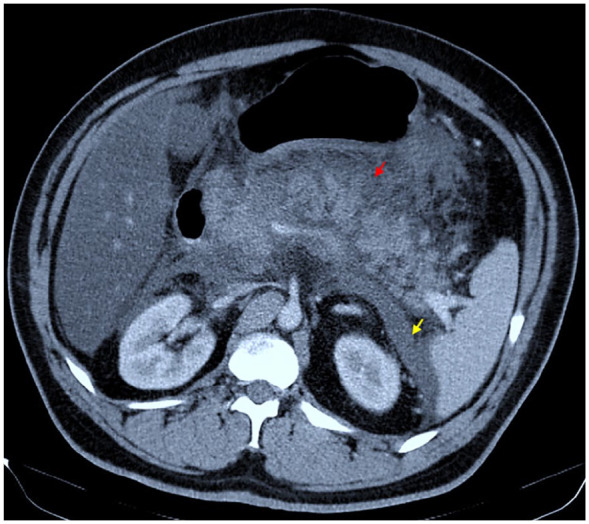

Diabetic ketoacidosis (DKA) is an acute complication of diabetes that mainly occurs in type 1 diabetes. However, it can also occur in type 2 diabetes, although less commonly. One of the rare causes of this condition is acute pancreatitis. While hypertriglyceridemia is a known complication of DKA, triglyceride levels higher than 2000 are an unusual finding. We present a case of undiagnosed type 2 diabetes mellitus in a patient who came to the hospital with epigastric pain, nausea, and vomiting. Subsequent blood tests revealed hyperglycemia, ketonuria, metabolic acidosis, and increased levels of amylase and lipase, leading to a simultaneous diagnosis of DKA, acute pancreatitis, and very severe hypertriglyceridemia. In patients experiencing abdominal pain and severe diabetic complications, acute pancreatitis should always be considered as a possible diagnosis, and triglyceride levels should be tested to identify hypertriglyceridemia as a potential cause of pancreatitis or complications of DKA.